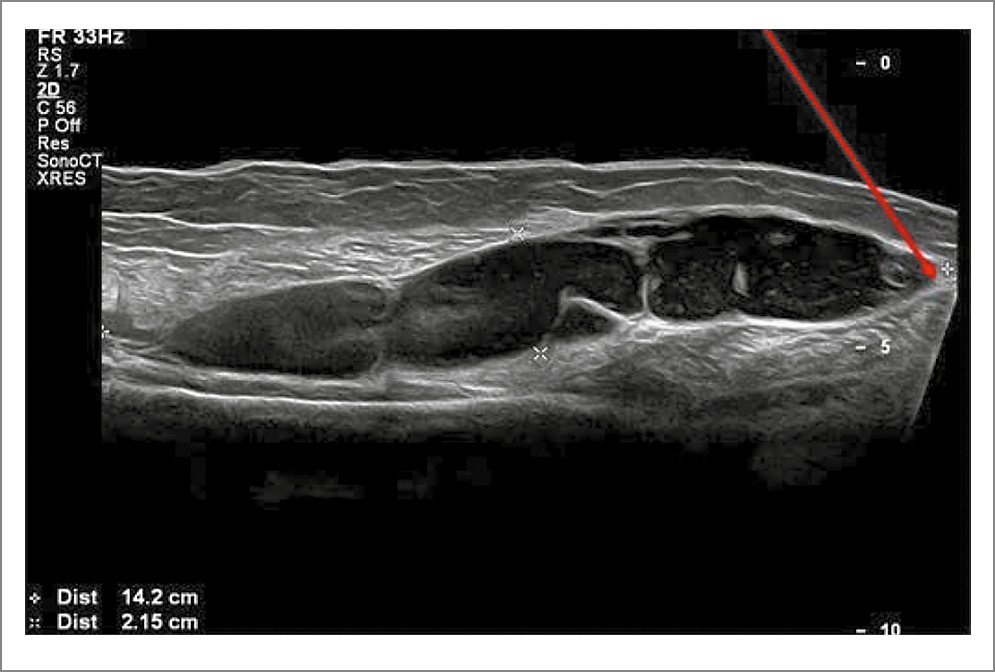

Наиболее доступным и эффективным методом верификации разрыва КБ является ультразвуковое исследование, которое позволяет визуализировать такие характерные признаки, как неоднородность структуры и деформация (заострение) нижнего полюса КБ, а также появление субфасциальных жидкостных прослоек вдоль сухожилия и/или брюшка медиальной головки икроножной мышцы (рис. 1, 2).

Рис. 1. Крупная многокамерная КБ (14,2×2,15 см) туго наполнена содержимым, имеется угроза разрыва. Нижний полюс кисты указан красной стрелкой.